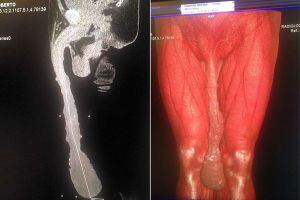

Roberto Esquivel Cabrera es un hombre común y corriente, con la única diferencia de que su pene ha alcanzado casi el medio metro de longitud, todo un récord.

Cabrera vive en una constante contradicción. Por un lado, sabe que su vida sexual es y será completamente nula pese a su virilidad, y trabajar se le dificulta sobremanera. Pero tampoco quiere reducir el tamaño de su miembro. Prefiere no pasar por el quirófano, como ya se le recomendó

A pesar de las recomendaciones para que se operara, Cabrera se ha negado "No aceptó (la cirugía), quiere tener un pene más grande que el resto de las personas. En la cultura latina, quien tenga el pene más grande es más macho. Es algo que lo hace diferente del resto de la gente y lo hace sentir especial", señala Jesús David Salazar González, el médico que intentó convencerlo de reducir el tamaño de su miembro.